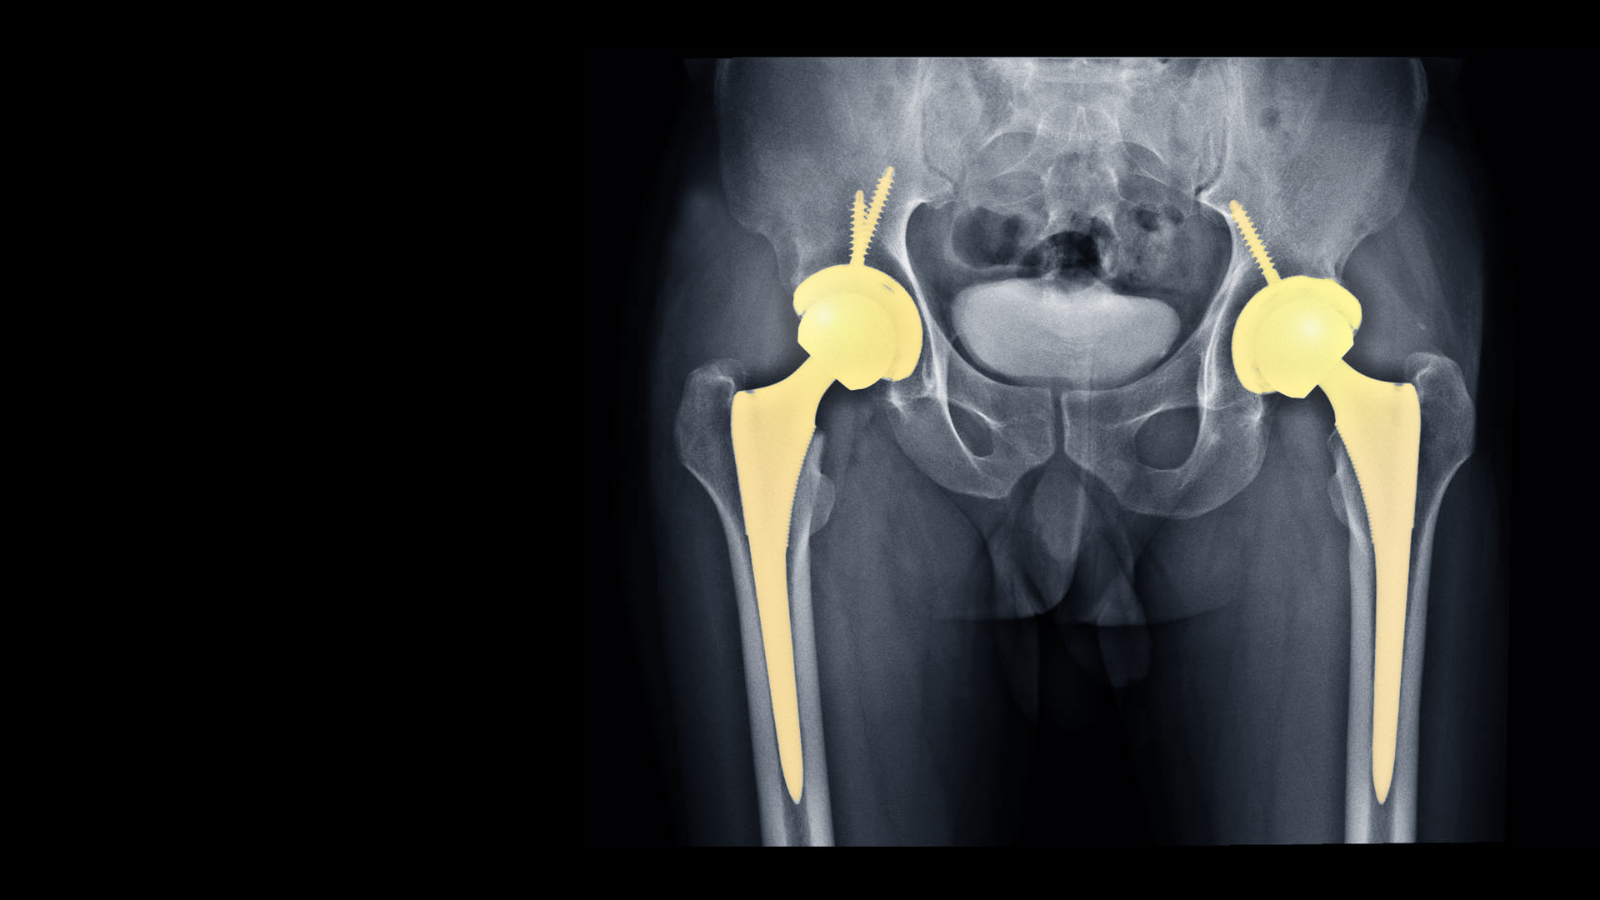

The total hip replacement involves replacing the damaged sections of the hip joint with an artificial joint (prosthesis).

The total hip replacement, also called total hip arthroplasty involves replacing the damaged sections of the hip joint with an artificial joint (prosthesis). Such artificial joint is usually made of metal, ceramic, and very hard plastic. The conventional total hip replacement will be performed through a 10 to 12 inches long incision made on the side of the hip.